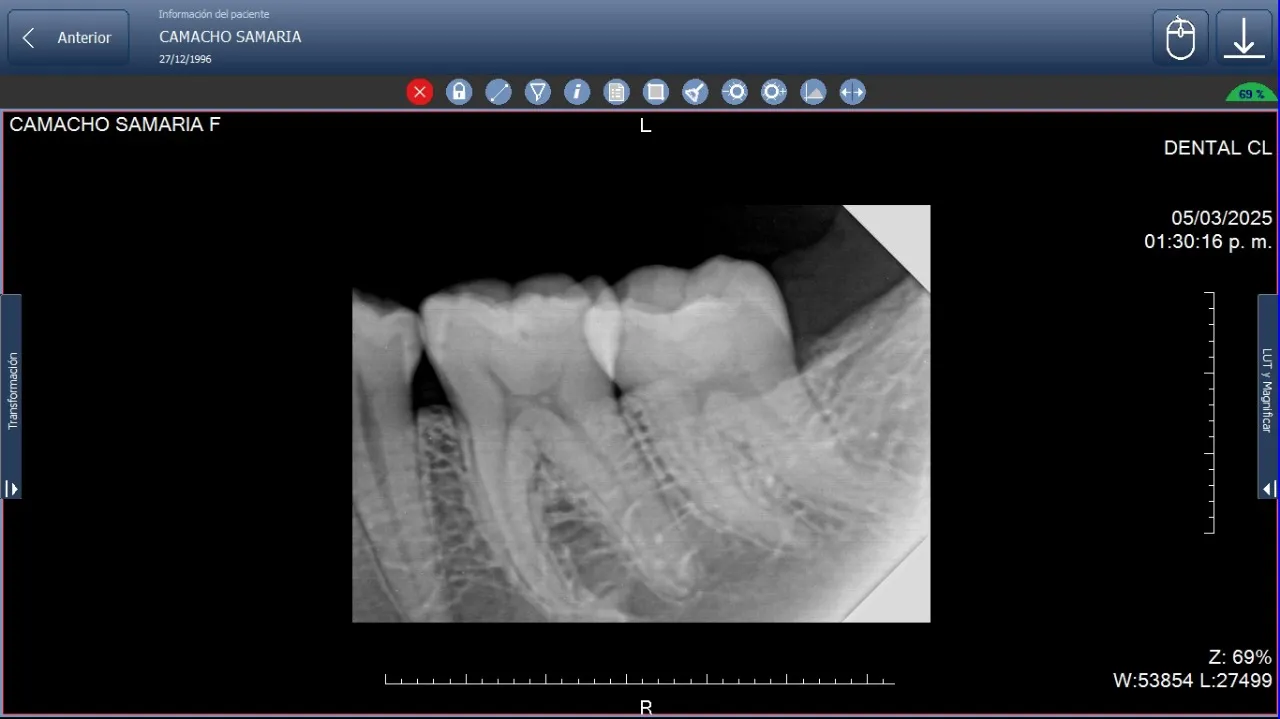

Imagen digital muestra radiografía periapical de dos muelas mediante los rayos X intraorales aplicaciones y cuidados del paciente.

Las radiografías intraorales son esenciales para la evaluación detallada de piezas dentarias individuales y sus estructuras de soporte. Dentro de los rayos X intraorales aplicaciones y cuidados del paciente, se incluyen procedimientos periapicales que permiten visualizar la totalidad de la pieza dentaria desde la corona hasta el ápice radicular, incluyendo el hueso circundante.

• Ofrecen una visión completa de toda la pieza dentaria, incluyendo raíz y tejidos circundantes.

• Son esenciales para detectar lesiones periapicales y evaluar tratamientos endodónticos.